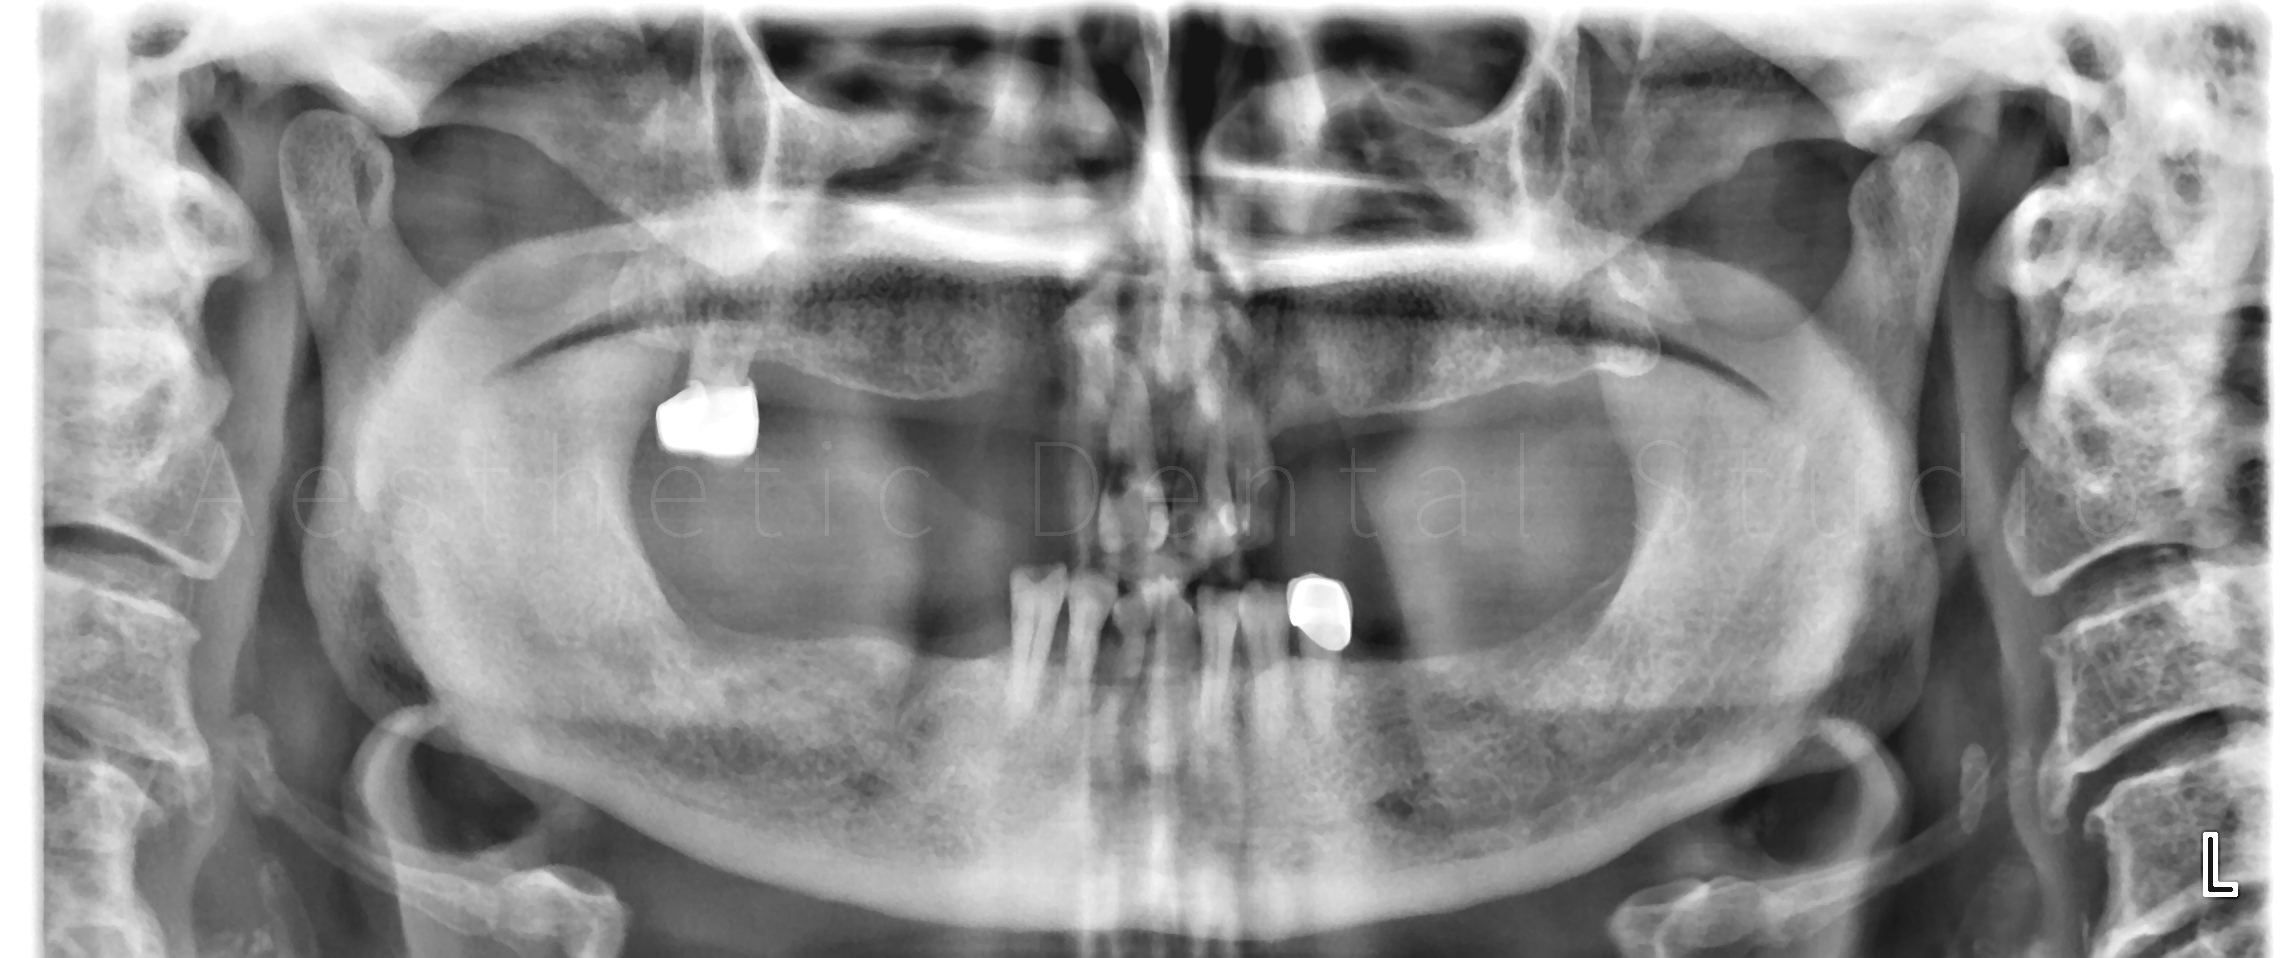

Στην πρώτη φάση, πραγματοποιήθηκε πλήρης αποκατάσταση της στοματικής υγείας, με αφαίρεση των εναπομείναντων δοντιών της άνω γνάθου, αφού αυτά κρίθηκαν μη αποκαταστάσιμα. Παράλληλα διατηρήθηκαν τα κάτω πρόσθια δόντια και αποφασίστηκε η μετέπειτα προσθετική αποκατάστασή τους. Στην συνέχεια, ακολουθήθηκε χειρουργική τοποθέτηση εμφυτευμάτων σε στρατηγικές θέσεις με πλήρως ψηφιακό πρωτόκολλο:

Με εξειδικευμένο οδοντιατρικό λογισμικό έγινε ψηφιακός σχεδιασμός και εικονική τοποθέτηση των εμφυτευμάτων, ώστε να εξασφαλιστεί απόλυτη ακρίβεια και ασφάλεια.

Αυτός ο οδηγός χρησιμοποιήθηκε στο χειρουργείο για την τοποθέτηση συνολικά 11 εμφυτευμάτων με ακρίβεια χιλιοστού:

• 6 στην άνω γνάθο

• 3 στην κάτω δεξιά περιοχή

• 2 στην κάτω αριστερή περιοχή